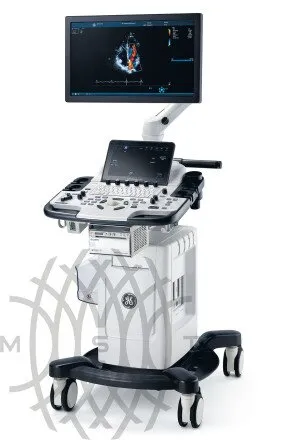

Ультразвуковой аппарат GE HealthCare Vivid T9

GE HealthCare Vivid T9 — универсальная ультразвуковая система для кардиологических и общих исследований у взрослых и детей, с расширенными возможностями диагностики в акушерстве и гинекологии, ангиологии, урологии, исследовании органов брюшной полости, малых органов, поверхностных структур и мышечно-скелетной системы, урологии, транскраниальных и чреспищеводных исследованиях. Ультразвуковая система среднего класса Vivid T9 объединяет признанное качество визуализации в кардиологии, характерное для линейки Vivid, и возможности широкого использования в общей диагностике, которыми отличается линейка LOGIQ.

Система предназначена для обеспечения удобства работы и транспортировки в различных условиях. Ее интуитивно понятный пользовательский интерфейс представляет собой саму консоль Vivid со всеми преимуществами ее приложений, функций, оптимизированного рабочего процесса, надежности и простоты в использовании. GE Vivid T9 идеально подходит для использования в многопрофильных медицинских учреждениях, специализированных диагностических центрах и кардиологических клиниках.

Универсальная система Vivid T9 обеспечивает превосходное качество изображений широкого спектра исследований и может быть настроена в соответствии с потребностями учреждения.

Удобство

Наслаждайтесь преимуществами простого и надежного сканирования. Система Vivid T9 предназначена для обеспечения удобства работы и транспортировки в различных условиях. Ее интуитивно понятный пользовательский интерфейс представляет собой саму консоль Vivid со всеми преимуществами ее приложений, функций, оптимизированного рабочего процесса, надежности и простоты в использовании.Расположение сенсорного экрана, поворотных регуляторов и функциональных кнопок удобно для пользователя, а все режимные кнопки собраны в одном месте рядом с трекболом.

Регулируемая консоль

Отрегулируйте консоль по оптимальному положению сканирования

Исключительная мобильность

Благодаря малому весу, составляющему всего 58 кг (128 фунтов), а также прочности колес и передних и задних ручек систему Vivid T9 легко перемещать по плитке и коврам.